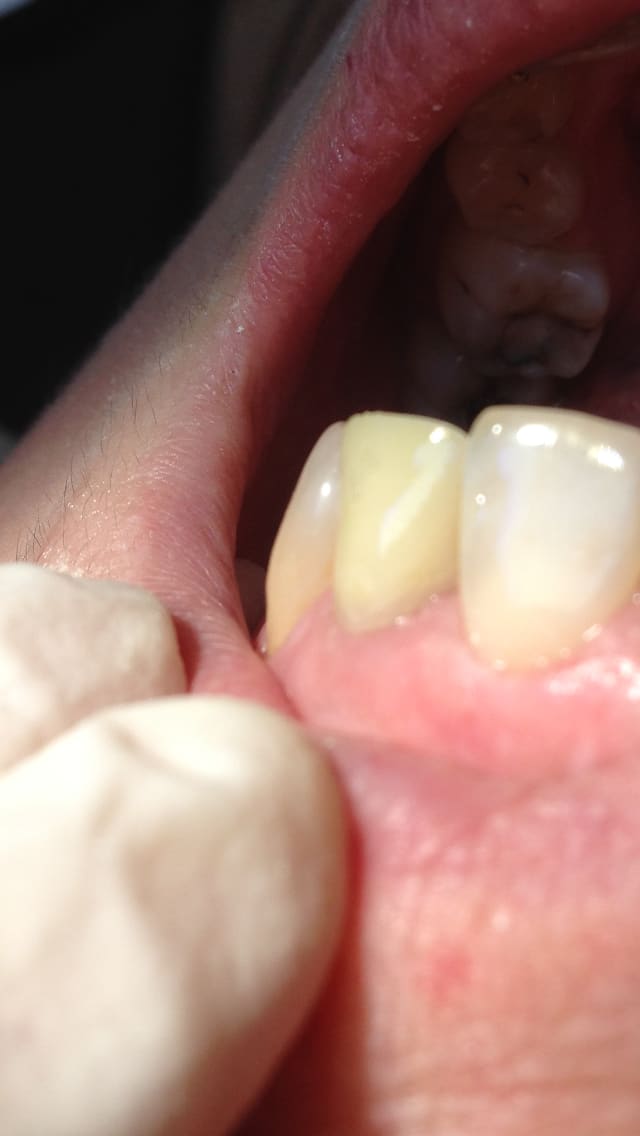

Patiente qui a une lésion sur son incisive latérale

1) je lui enlève la couronne et IC

j'instrumente j'irrigue je laisse l'hypochlorite je remets IC couronne

2) 2eme RDV

J'irrigue en profondeur

J'obture à LT - 2

J'enfile un gros instrument chaud pour balancer la substance chaude et blanche à LT-1

Je fais ma provisoire